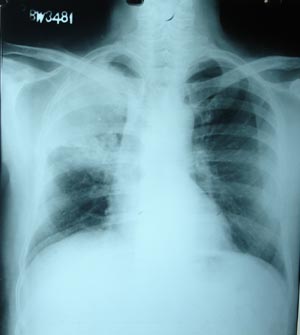

Pulmonary tuberculosis 2

The most obvious radiographic abnormality is the right upper lobe infiltrates with atelectasis and an air bronchogram visible most readily in the CT scan. There is also opacification of the right lower lobe due to infiltrates. This pneumonic form of tuberculosis is more difficult to discriminate from conventional bacterial infectious processes. Tracheal pull on affected side is visible.